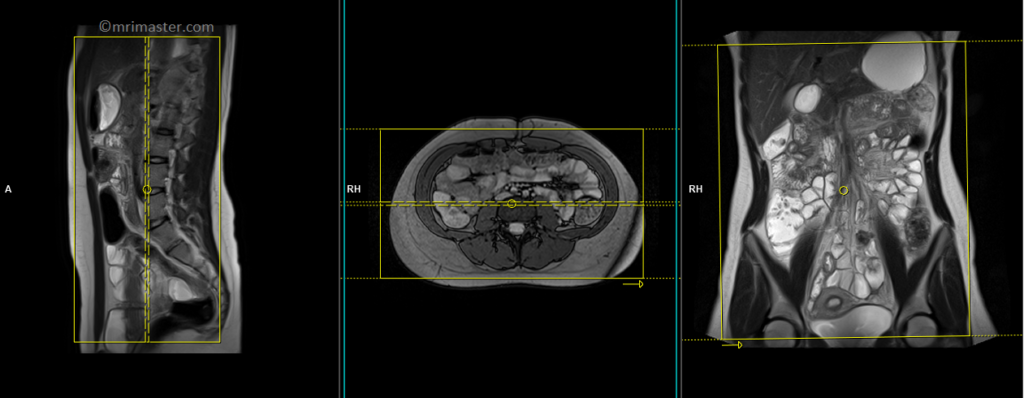

T2 TRUEFISP axial

Plan the axial slices on the coronal image, position the block horizontally across the abdomen as shown, and ensure that the positioning block is also checked in the other two planes. Establish an appropriate angle horizontally across the abdomen in the sagittal plane. The slices must be sufficient to cover the entire abdomen and pelvis from the stomach to the pubic symphysis. Phase oversampling can be used to avoid wrap-around artifacts. Instruct the patient to hold their breath during image acquisition.

The axial scan is performed as two separate blocks with a 20-30% slice overlap between them. The scan is performed this way to avoid any RF inhomogeneity-related artifacts by conducting the scans at the isocenter of the magnet. Use the composing function in the scanner to stitch the two blocks together.